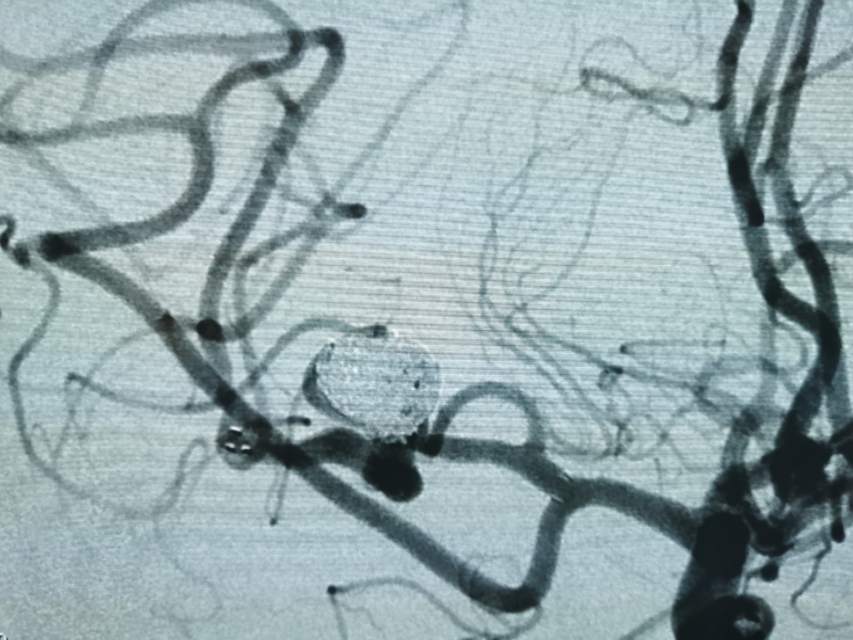

如何将“基底型动脉瘤”转型为“侧壁型动脉瘤”?

福建中年女性,近期在外查出“颅内动脉瘤”,经推荐转来我院诊治。患者的颈内动脉通路迂曲,动脉瘤也位置奇特,解剖复杂,动脉瘤远近段的血管弯弯绕绕,重重叠叠,眼花缭乱,难以兼顾找到最佳位置。最终克服困难,将“基底型”动脉瘤改变为“侧壁型”动脉瘤,顺利给予治疗……